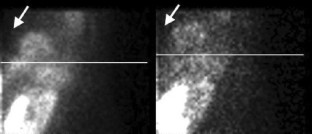

The truncation artifact

Figure 1